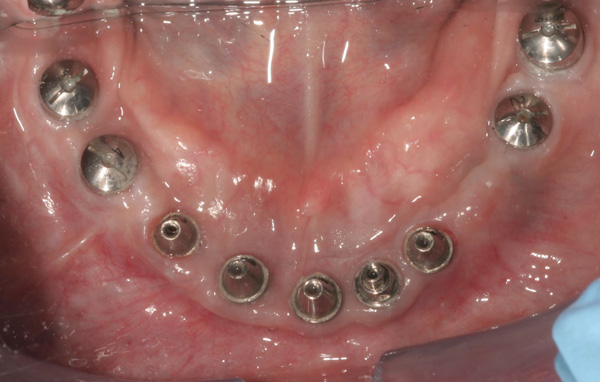

Background: This patient had a failing maxillary dentition and refused to wear a removable prosthesis. A staged approach was employed to retain some of his natural tooth abutments, and recession was noticed at the time of the impression for the second group of implants. Figure 1 shows the patient following insertion of the first set of implant custom abutments; the adjacent natural teeth are still present to support the provisional bridge. Seven months later, as shown in Figure 2, those first-stage custom abutments exhibited evidence of 1 mm to 3 mm of recession.

Figure 1 Patient following insertion of first set of implant custom abutments.

Figure 1